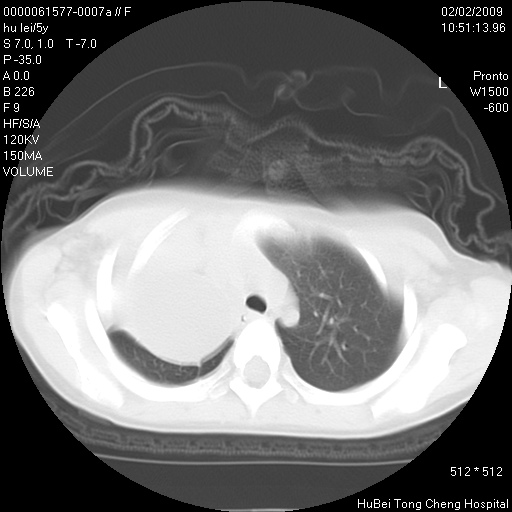

标题: PED1732:M5Y,右肺囊性占位!

患者:男,5。无明显不适,拍胸片考虑右肺囊肿。

行ct扫描,图象如下:

考虑先天性巨大支气管肺囊肿,建议包虫实验除外肺包虫。

右肺巨大囊性占位性病变;考虑巨大肺囊肿,不排除淋巴管瘤可能。